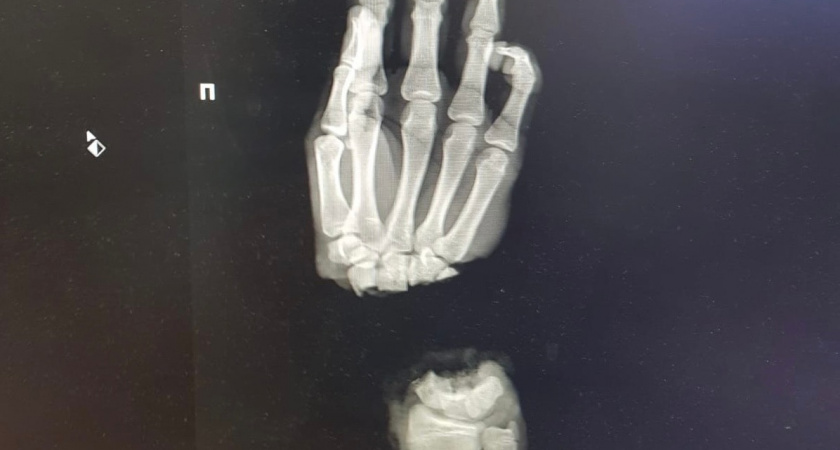

Подростка привезли в университет 1 марта из Коврова. Как выяснилось, он колол дрова и случайно отсек себе кисть. Операцию провели в тот же день вечером. На данный момент молодой человек в стабильном состоянии, кровоснабжение в его руке восстановлено. Однако понадобится еще несколько операций, чтобы он снова мог владеть рукой, насколько это возможно.